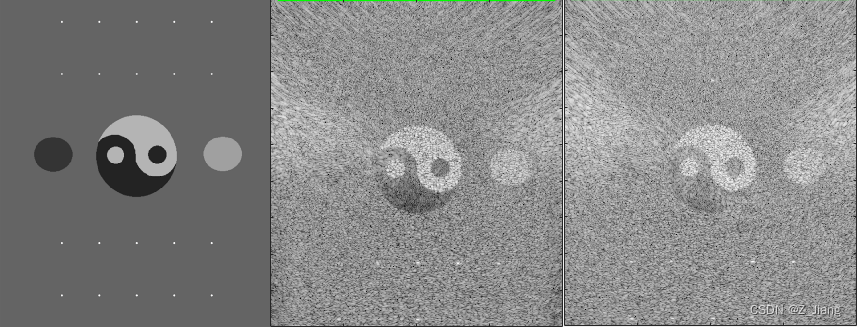

左:体模 中:单次全孔径平面波 右:单次全孔径发散波

扩散波与平面单次发射,全区域成像结果比较类似。我们可以发现,这两种发射由于成像区域内没有焦点,也就不存在无声区,即使我做到512的MLA覆盖4厘米的宽度,也不会出现暗黑的无声区域。另外,大家应该留意到MLA的BLOCK格子也不会存在。因为声压全场统一,不会由于不同的MLA线处声压强度,导致MLA线实际位置横向偏移,同时这种极端扫查情况下,帧速率(FPS)可以做到每秒几千甚至上万。可以把这样的优势用在需要高帧速的场景,更精细的运动追踪,时间解析度更高的造影等等。

但缺点也很明显,grating lobe伪影明显,信噪比低,分辨率差等。在实际系统设计上,我们肯定使用更小的孔径,更少的MLA,多次发射,降低FPS,来平衡图像品质。

在具体说合成孔径之前,大家先看效果,对比一下,有个直观印象先。下边右图是进行23组合成孔径的效果,偏转角度从-15度至15度,发射是全孔径激励的平面波的成像结果,中间是单次平面波无偏转,全孔径激励的平面波的成像结果,左图是原始体模;

合成孔径对超声图像的提升是显而易见的。为了更直观的表达,下面的动画展示了进行31次合成孔径的处理过程中带来的变化,由于旋转了31个角度,波阵面各有不同,所以每个角度实际上也进行了类似聚焦波的RTB处理,效果如下: